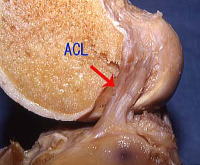

膝関節靱帯損傷

前十字靱帯損傷

前十字靭帯損傷(ACL: anterior cruciate ligament injury)は、膝関節内血腫があっても骨折所見などないため見逃されることが多い損傷です。

スポーツでの怪我による外傷が多く、とくにジャンプの着地時やテニスなどの捻り動作時にがくっと膝崩れするとともに発症します。その際にはバシッと音を感じることが多いようです。

当初の痛みは10-60分ほどで少し軽くなるため帰宅し様子みる方が多いのですが、徐々に関節内に血がたまり、6-12時間で痛みが極めて強くなり、翌日に来院されることが多くなります。

診断は膝前十字靱帯損傷の陳旧例では膝関節前方動揺性テストまたは回旋不安定テスト(Jerk test)は高率に出現しますが、急性期では痛みのためにテストが困難な例が多くなります。関節内血腫と受傷機転などから前十字靭帯損傷を疑ってMRI検査、関節鏡検査を行う必要があります。

治療は新鮮前十字靭帯損傷は一部を除き、ギプス固定では治癒しないこと、放置した場合3-5年で二次的半月板損傷、さらにそれ以上の年数で変形性関節症変化の合併率が高くなることから、45歳以下で活動性の高い方に手術的治療が薦められます。複合靭帯損傷や半月板損傷合併例は手術が第一に薦められます。

手術をしない場合は運動時には、膝靱帯サポーターを必ずつけるなどの注意が必要です。前十字靱帯不全の症状は軽く膝が抜けるくらいなので軽く考えがちですが、月に1度位でも繰り返していますと、次第に変形が進み、半月板損傷も合併しますので、運動時のサポーター着用など忘れないようにしてください。

しかし、数年はよくても、徐々に2次的障害が進むのは避けがたくなります。新鮮前十字靱帯損傷例に対する一次修復術(縫合術)の成績は一定しないため、一般にはあまり行われなくなりました。現在は前十字靭帯完全断裂の場合、50歳台以下の方であれば、前十字靱帯再建術で治療することが薦められます。

最新の治療では前十字靭帯部分損傷で不安定性高くなければPRP治療(動画)で良好な成績が発表されておりPRP治療も推奨の選択肢です。

横からみたACL